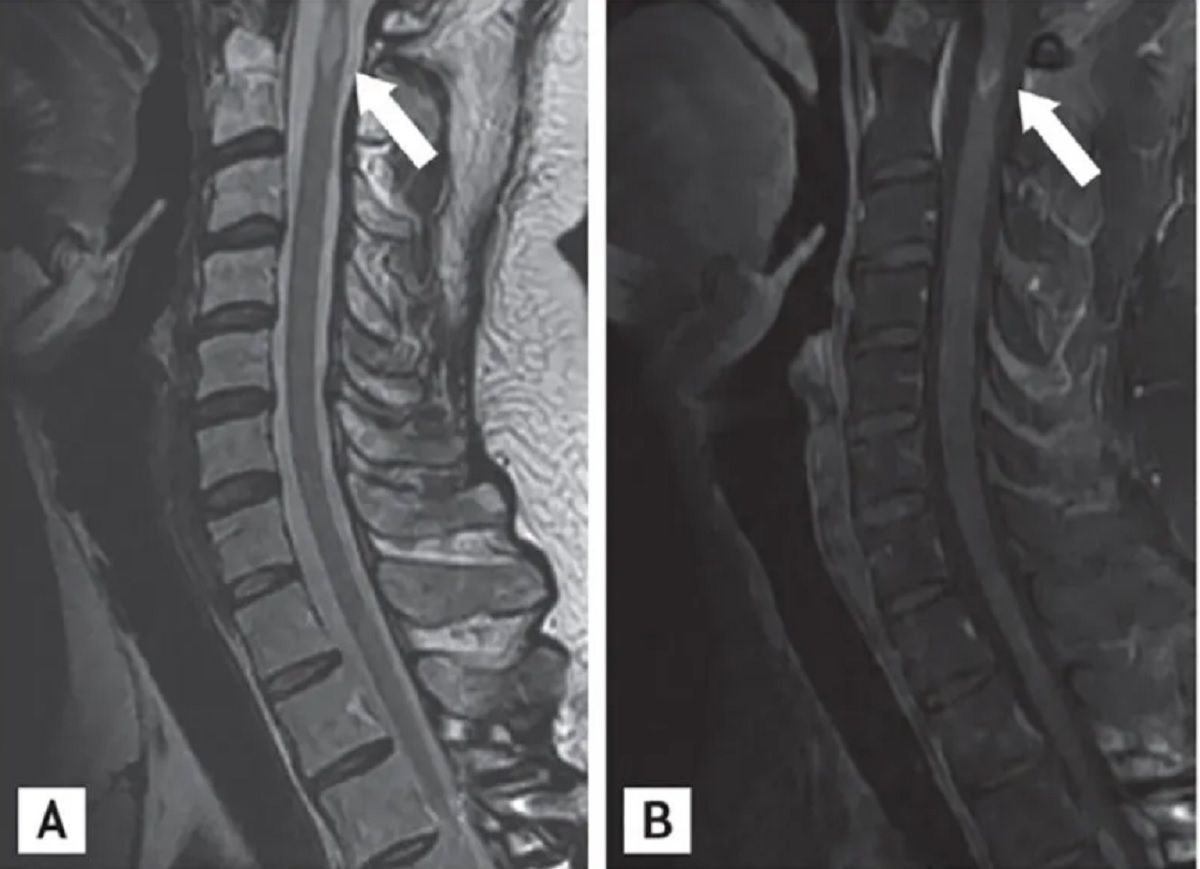

Săgețile indică leziuni intramedulare sau leziuni din măduva spinării. Leziunile intramedulare pot fi cauzate de o tumoare, infecție sau inflamație, care este cauza în SM. Yoon BN, Ha CK, Lee KW, Park SH, Sung JJ. A confusing case of multiple sclerosis and central nervous system graft versus host disease. Korean J Intern Med. 2016;31(5):995-998. doi:10.3904/kjim.2015.065